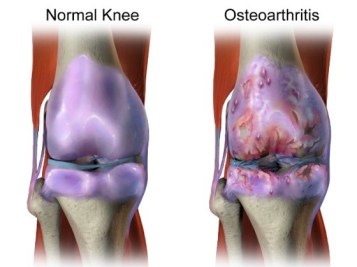

Osteoarthritis occurs when the articular cartilage that lines the surfaces of the joints becomes damaged. This can happen due to acute trauma, or as a result of aging.

ith almost no new matrix synthesis or breakdown. However, in response to injury, disease or aging, articular chondrocytes begin to break down matrix at a faster rate than they replace it. The result is formation of focal lesions of cartilage loss, known as articular cartilage defects, which eventually expose the underlying bone in large areas of the joint surfaces. These defects prevent smooth gliding motion of the joints and the exposed bone causes intense pain for patients. The end result of these changes is Osteoarthritis.

As no clinical approach is yet effective in treating Osteoarthritis, the key is prevention by restoring focal articular cartilage defects before damage becomes widespread. Clinical approaches for cartilage repair include filling the defects with pieces of donor cartilage, chondrocytes, or injections of “stem” cells obtained from fat or bone marrow. These attempts have not produced consistently durable articular cartilage repair. We propose this is because the cells used for repair in these clinical approaches don’t have the innate ability or preference to form native articular cartilage tissue.